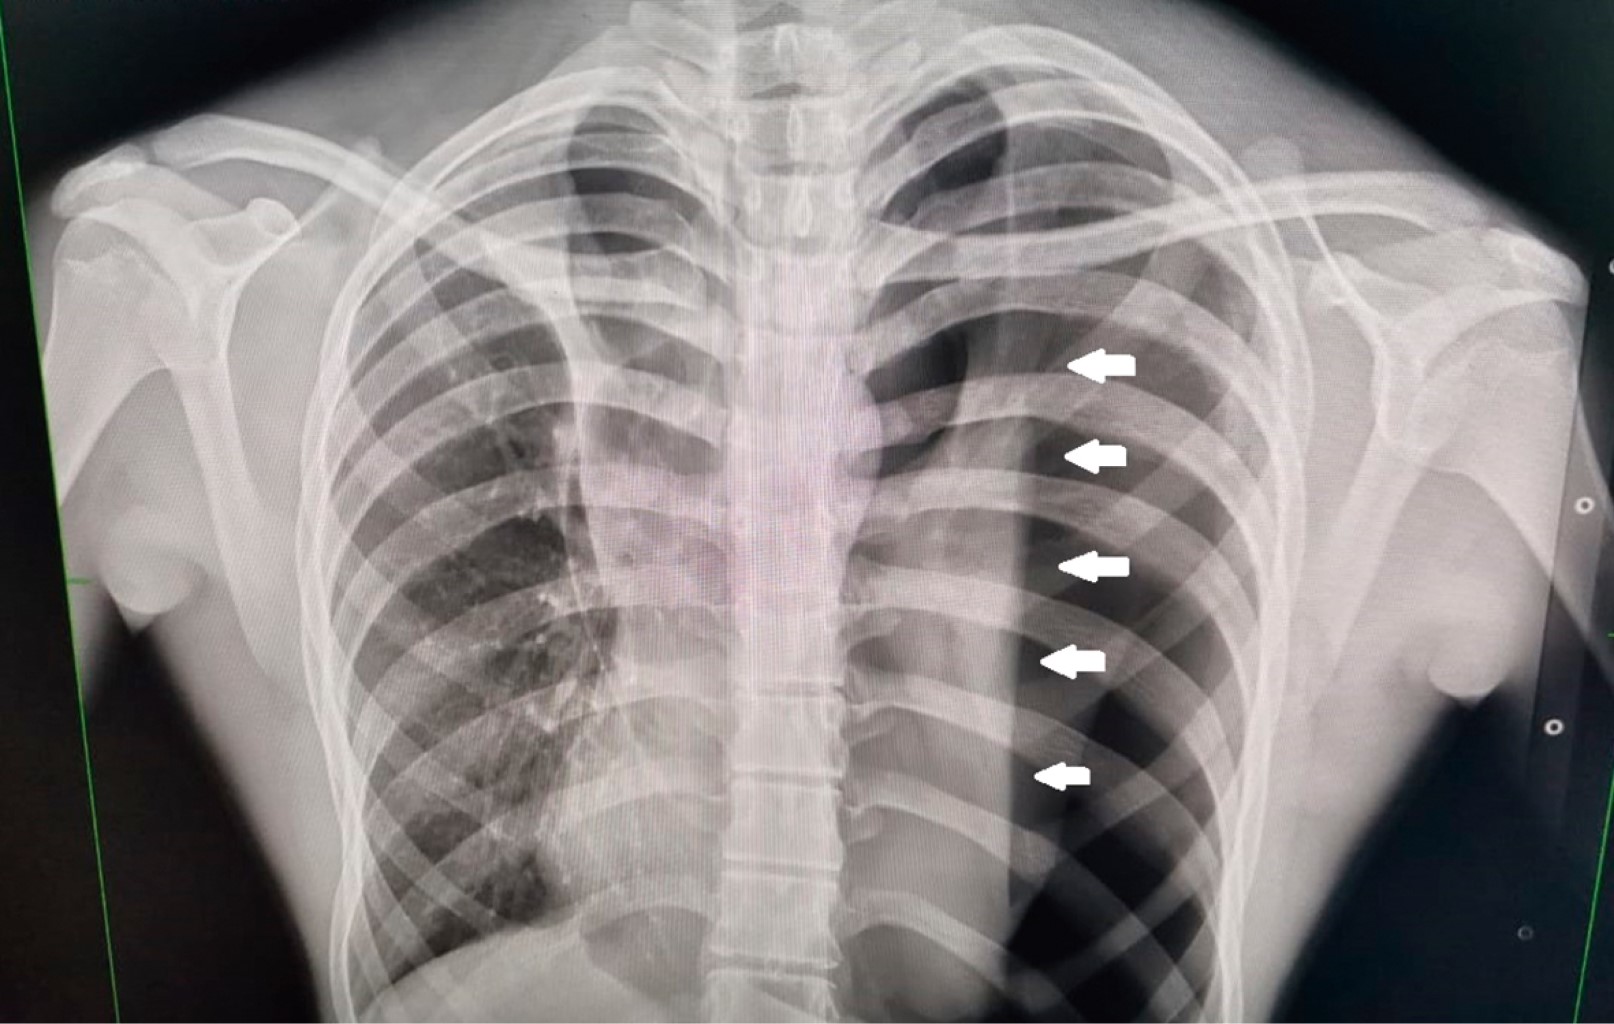

El tres semanas después acude al servicio de urgencias refiriendo dolor en hemitórax izquierdo de dos días de evolución, de inicio súbito, transflictivo, así como disnea en reposo, a la exploración física con hipoventilación de hemitórax izquierdo e hiperresonancia a la percusión, en la radiografía se observa neumotórax recidivante (Figura 1) y se coloca sonda endopleural, con adecuada expansión pulmonar (Figura 2) y buena evolución clínica, siete días después se realiza prueba con sonda pleural a sello, presentando disnea y dolor torácico, en radiografía de control se aprecia neumotórax izquierdo recidivante (Figura 3), por lo que se solicita tomografía computarizada observándose persistencia de neumotórax y bulla apical izquierda, por lo que se inicia protocolo quirúrgico para toracoscopia.

Figura 2